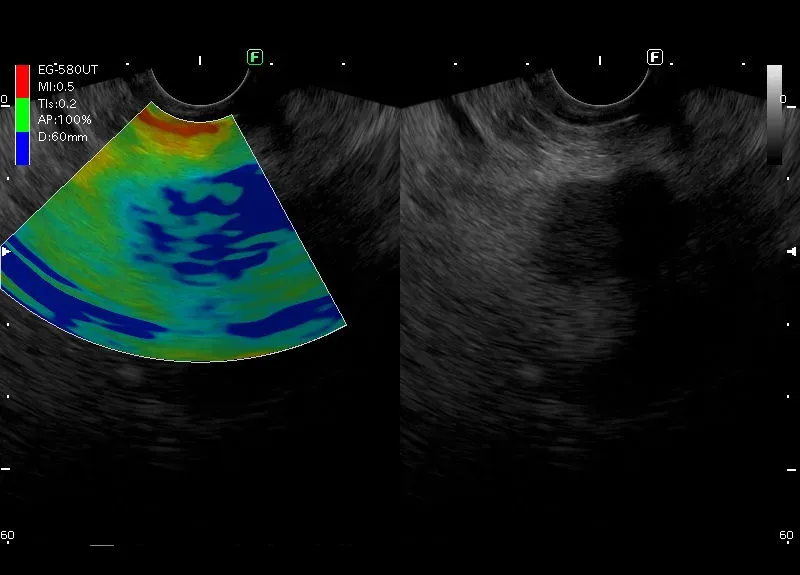

Zmiana kodująca się na niebisko - „zmiana twarda” w elastografii.

Zmiana położona w głowie trzustki o niejednorodnie obniżonej echogeniczności, nierównych zarysach i wielkości około 23/30mm. W badaniu power doppler widoczny jest dyskretny przepływ obwodowy.

Całokształt obrazu odpowiada guzowi trzustki.